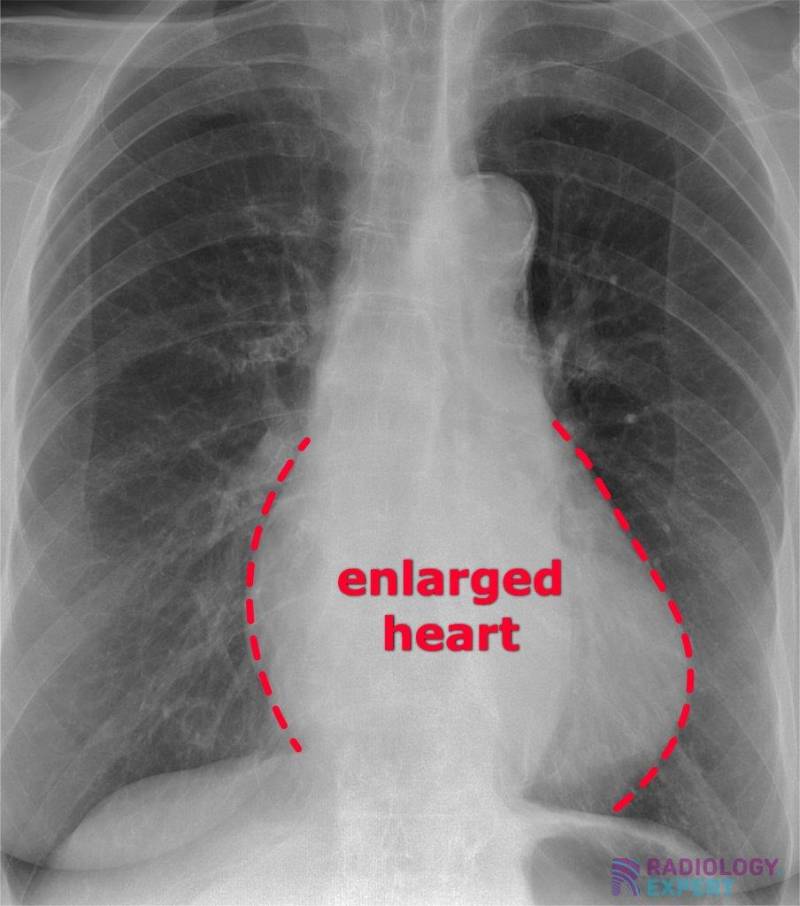

Heart failure How does it appear on a chest Xray?

From www.radiology.expert